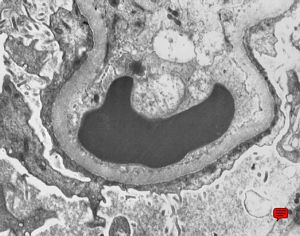

M,22y. | type II membranoproliferative glomerulonephritis